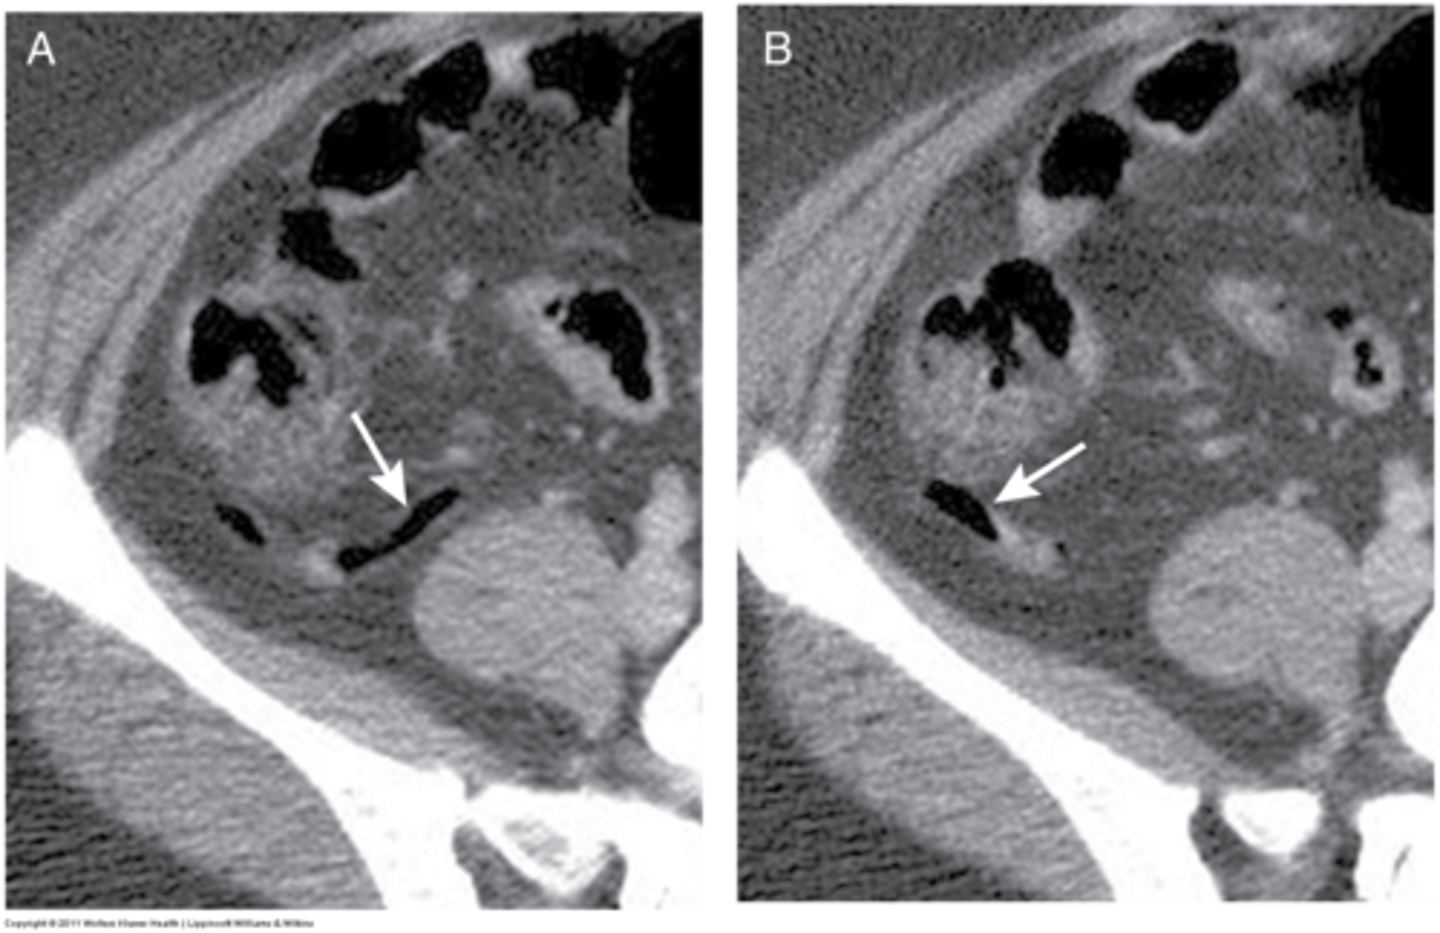

diverticulosis

outpouchings of colon, uncertain etiology, 90% pts asymptomatic, some pts have chronic constipation, abdominal pain, fluctuating bowel habits

diverticulosis CT

air filled outpouchings of colon that represent diverticula

diverticulitis

macroscopic inflammation of a diverticulum, may lead to microperforation, abscess, or peritonitis

S/Sx: aching LLQ pain, N/V, constipation or loose stools

Abdominal CT + f/u Colonoscopy or CT colonography